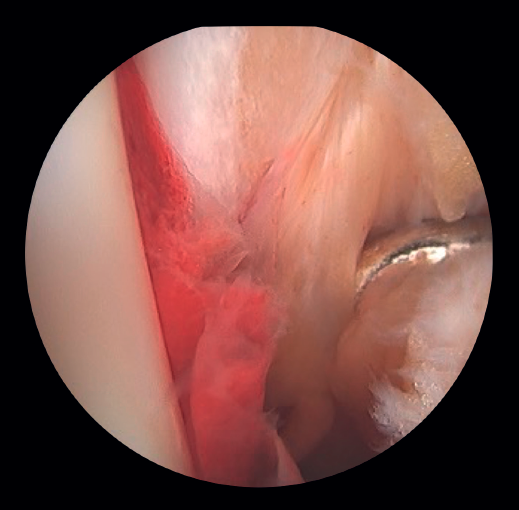

- Assessment of the deltoid ligament. Tearing of the deltoid ligament can cause persistent medial instability after reduction of the fibula, associated with pain, dysfunction and the risk of PTOA if not adequately treated. Its repair in acute ankle fractures has been shown to improve reduction of the medial clear space (MCS) and the functional outcomes (AOFAS), and reduce postoperative complications. In SER type fractures, the assessment of medial stability is essential: while in SER II fractures the deep fascicle of the deltoid ligament is usually preserved, in SER IV fractures there is complete medial injury that compromises the tibiofibular mortise and requires surgical treatment(19).

In fractures with deltoid ligament damage, an increase in intra-articular injuries, such as osteochondral lesions, has been reported(19).

If the deltoid ligament injury involves only the anterior part, arthroscopic reinsertion can be made using resorbable implants. If deltoid ligament disinsertion is complete, open reinsertion is preferred, because of the difficulty of placing the implants in the posterior malleolus and the risk of neurovascular injury (Figure 5).